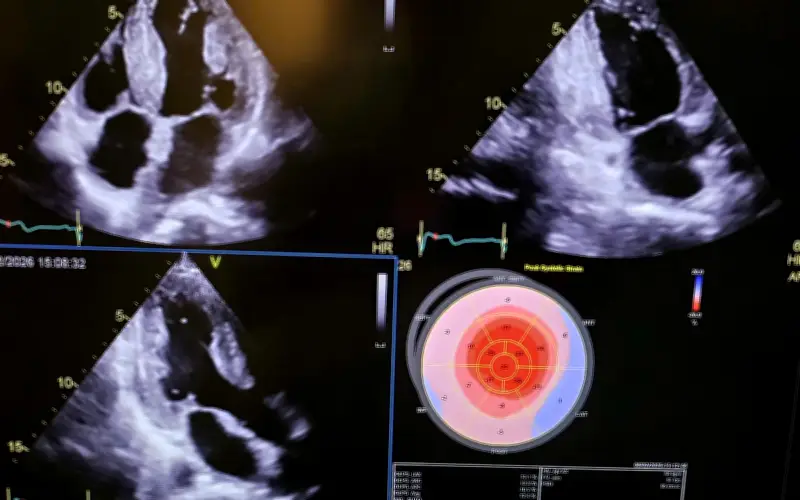

Ca phẫu thuật này được đánh giá là cực kỳ phức tạp do liên quan đến việc ghép đồng thời hai cơ quan quan trọng là tim và gan. Quy trình yêu cầu sự phối hợp nhịp nhàng giữa nhiều chuyên gia hàng đầu trong các lĩnh vực như tim mạch, gan mật, gây mê hồi sức và hậu phẫu. Thời gian phẫu thuật kéo dài nhiều giờ, đòi hỏi độ chính xác cao và công nghệ hiện đại để đảm bảo an toàn tối đa cho bệnh nhân.